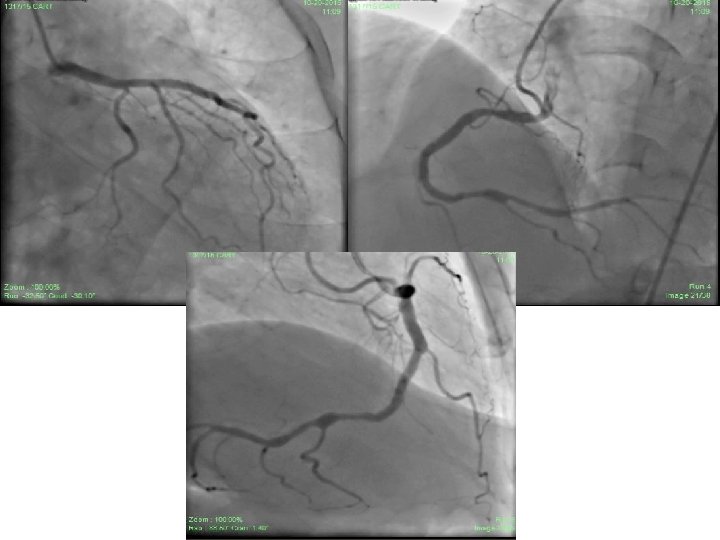

• Check angiography done after 2 months showed normal flow through and beyond stents with TIMI – III flow (both RCA and LAD stents). • Proximal RCA – 40% stenosis, Crux and PLV - 50% stenosis with D 1 showing TIMI – III flow.